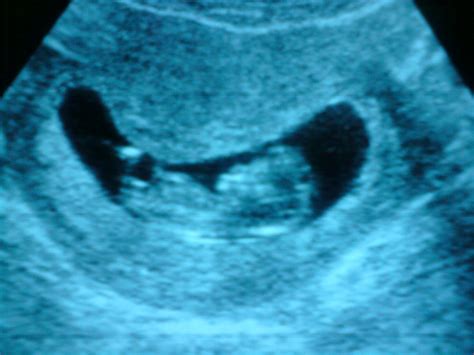

The Crown Rump Length is typically measured during an early ultrasound, often performed between 7 and 13 weeks of gestation. The procedure is usually carried out via a transvaginal ultrasound in the very early stages for better clarity, or an abdominal ultrasound as the pregnancy progresses slightly.

During the scan, the sonographer identifies the top of the baby’s head and the bottom of the rump. They then use electronic calipers on the ultrasound machine to mark these two points. The software calculates the distance between them, and the computer instantly cross-references this value with gestational age databases to provide a measurement in millimeters (mm).

The Crown Rump Length is defined as the measurement of a fetus from the top of its head (the crown) to the bottom of its buttocks (the rump). Because fetuses typically spend the first trimester curled in a fetal position, it is impossible to measure them from head to toe. Therefore, this measurement excludes the length of the legs, which are tucked in, making the CRL the most accurate way to assess the size and age of an early-stage embryo or fetus.